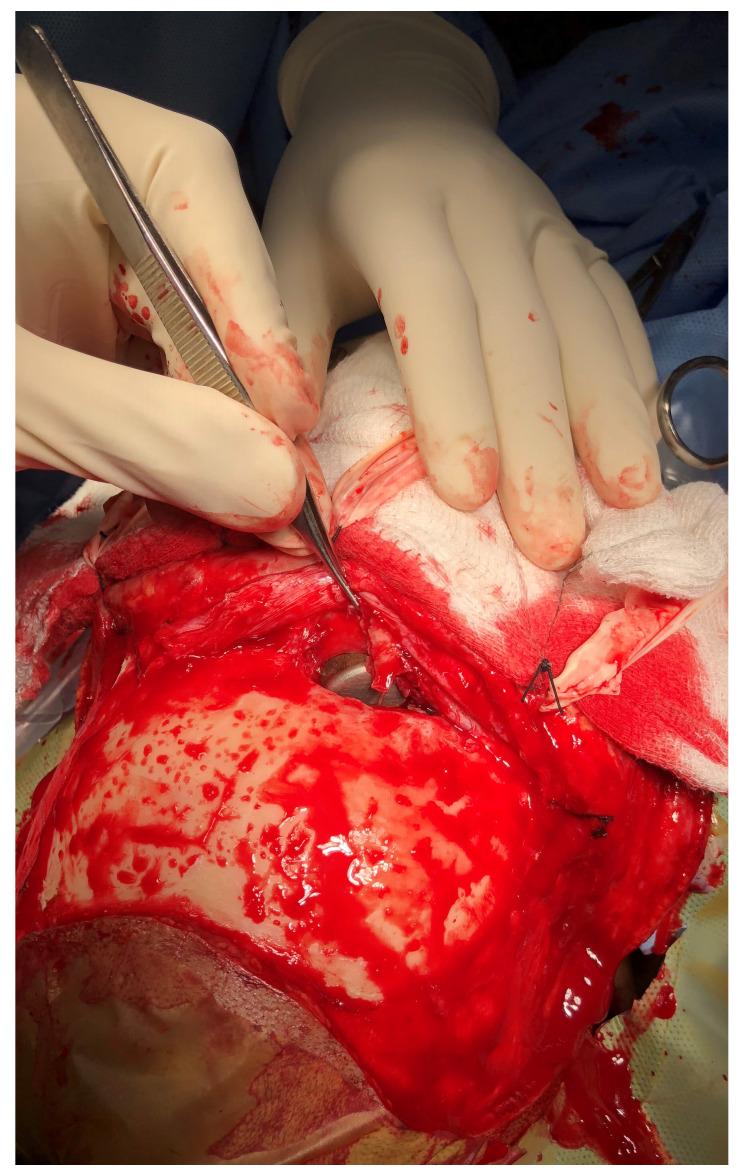

There are a number of ways in which one can sustain a head injury. Even if you are doing simple household activities or going out for a morning walk, you cannot be sure of what type of injury awaits you. The source of injury may be a pressure cooker whistle acting as a projectile or a hailstone falling from the sky. Such injuries are common in Nepal, considering the socio-demographic and geographic conditions. In this article, we present two such very rare cases of head injury. The first case is a middle-aged woman who sustained an accidental injury to the face associated with fracture of frontal sinus and frontal contusion, following the impact from a high momentum projectile in the form of the pressure regulator of a pressure cooker. She underwent craniotomy and removal of the foreign body. In the second case, an elderly man sustained minor injury to the head following the fall of hail. The abrasions and contusions produced by the hail were managed conservatively. Since he did not have any clinical evidence of head injury, other than multiple abrasions with contusions in the scalp, he did not undergo any imaging studies. He did not have any neurological deficits. The postoperative period was uneventful for the first patient and she was followed up for one month. The second patient was lost to follow-up. Successful management of two very rare cases of head injuries from Nepal are reported. Proper care and maintenance of the house-hold utensils that are constantly used may protect people from head injuries. Though natural calamities cannot always be avoided, simple measures like using an umbrella while going outdoors may protect individuals from head injuries due to hailstones.

有许多种方式可能导致头部受伤。即使你只是在做简单的家务或晨练,也无法确定会遭遇哪种类型的伤害。伤害可能来自高压锅的哨子,它可能成为一个抛射物,也可能是天降的冰雹。在尼泊尔,由于社会人口统计学和地理条件的影响,这类伤害很常见。在本文中,我们介绍了两例非常罕见的头部受伤病例。第一例是一名中年女性,她在面部意外受伤,伴有额窦和额部挫伤,受伤原因是高压锅的压力调节阀以高动量抛射物的形式撞击。她接受了开颅手术和异物取出术。第二例是一名老年男性,他在被冰雹砸伤后头部受轻伤。对冰雹造成的擦伤和挫伤进行了保守治疗。由于除了头皮多处擦伤和挫伤外,他没有任何头部受伤的临床证据,因此没有进行任何影像学检查。他没有任何神经功能缺损。第一例患者的术后恢复顺利,随访一个月。第二例患者失访。本文报告了两例来自尼泊尔的非常罕见的头部受伤病例的成功治疗。对经常使用的家用器具进行适当的维护和保养,可能有助于防止头部受伤。虽然自然灾害无法完全避免,但像在户外时使用雨伞这样简单的措施,可能有助于防止因冰雹导致的头部受伤。